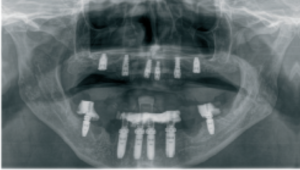

b. Planificación digital de la orientación de los canales de tornillo, con comparación entre canales rectos y angulados. Aplicación de canales de tornillo angulados para corregir la angulación del implante y desplazar la salida del canal lejos de la zona estética.

c. Situación clínica tras la fase quirúrgica del tratamiento, con colocación de implantes y prótesis provisional.